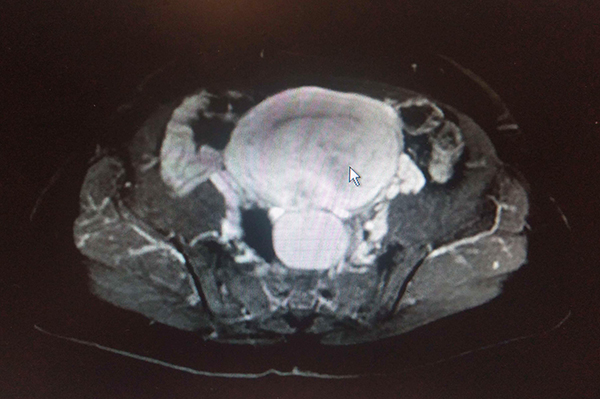

日前,葉女士因不規則陰道流血半個月在外院就診,發現子宮多發占位,隨即來到柳州市人民醫院婦科做進一步診治。經完善相關檢查后,葉女士除了子宮多發占位外,還發現左側腹部巨大占位,左側腹膜后占位,大小約10.0cm×13.8cm×16.0cm,腫物壓迫胰腺體尾部、左腎、左側腎上腺、鄰近腸管及脾臟,左側腰大肌受壓、變小,而且腫瘤位置特殊,臨近多個重要臟器,整個盆腹腔被腫瘤占滿,給治療帶來很大難度。

患者初步診斷為原發腹膜后腫瘤、子宮腫瘤、附件腫瘤。治療難度較大在于腹膜后腫瘤的切除,而且腫瘤常常會包繞、浸潤重要血管及局部臟器,給醫生帶來了極大挑戰。婦科二病區陳煜岊副主任介紹,腹膜后腫瘤由于位置深,通常情況下早期并無明顯的癥狀體征。而當患者感覺腹部脹滿或者摸到腹部包塊時,腫物往往已經巨大,腹膜后腫瘤手術需要多學科配合。婦科隨即組織了多學科聯合診療討論,制定了詳細的手術計劃。